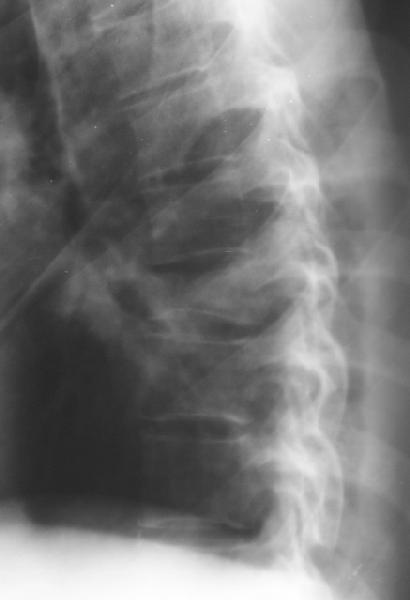

Перелом IX грудного позвонка |

Мужчина 39 лет, перевернулся в машине 12 июня. Клинически неврологии нет. Нужна ли репозиция и оперативная фиксация этого повреждения? Если нет, то как вести? Спасибо заранее.